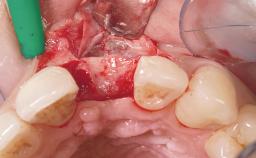

Early Placement of an Implant in a Maxillary Right Central Incisor Site

This 41-year-old female patient was referred to the clinic for the replacement of the right central incisor, since the tooth had developed a root fracture in the long axis that made extraction necessary. The healthy, non-smoking patient was first seen with the tooth still in place. A detailed Esthetic Risk Assessment was performed.The patient was worried about her dental esthetics and had high expectations for a successful treatment outcome from an esthetic point of view. The patient had a medium lip line that displayed parts of the gingiva in the anterior maxilla upon smile.

Bone Augmentation | Horizontal|Simultaneous |

Augmentation Materials | Autogenous chips|Xenogenous|Membrane |